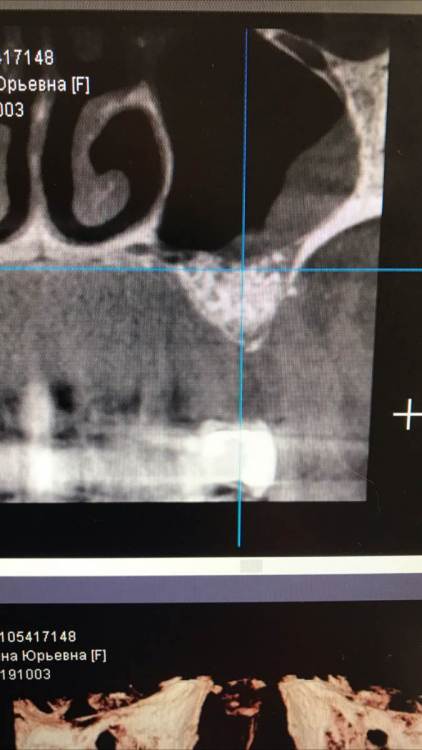

TIGER Опубликовано 18 февраля, 2022 Поделиться Опубликовано 18 февраля, 2022 Приветствую коллеги!Небольшой кейс с удалением кисты и синусом.Произведено :удаление кисты,синус-лифт ,через 4 месяца имплантация,ещё через 4 протезирование 5 1 1 Ссылка на комментарий